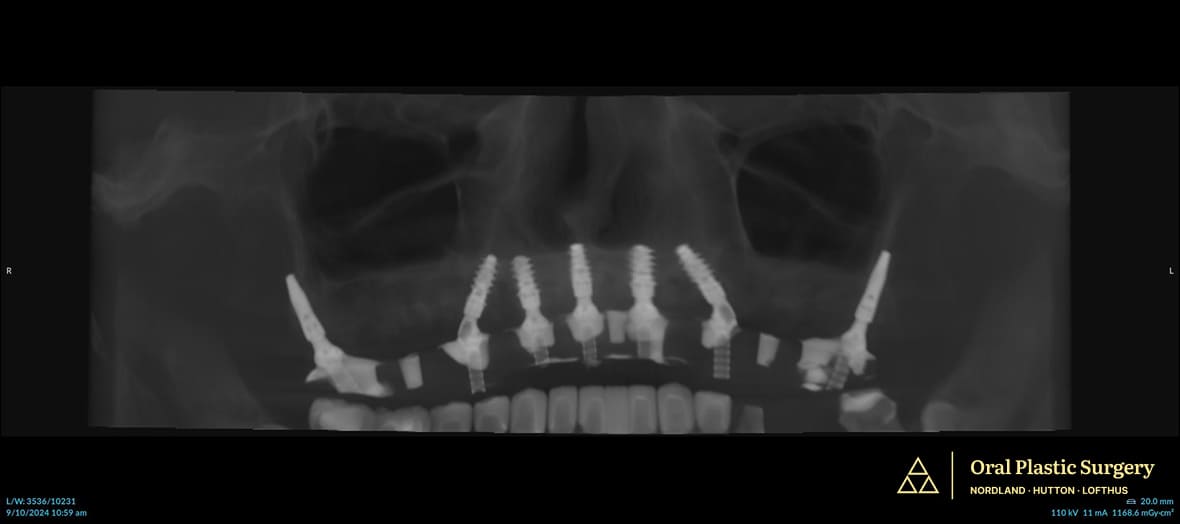

Post-surgery X-ray shows all seven implants in place. The pterygoid implants provide secure anchorage in the upper jaw, allowing Phil to regain molars and full chewing strength

Post-surgery X-ray shows all seven implants in place. The pterygoid implants provide secure anchorage in the upper jaw, allowing Phil to regain molars and full chewing strength.